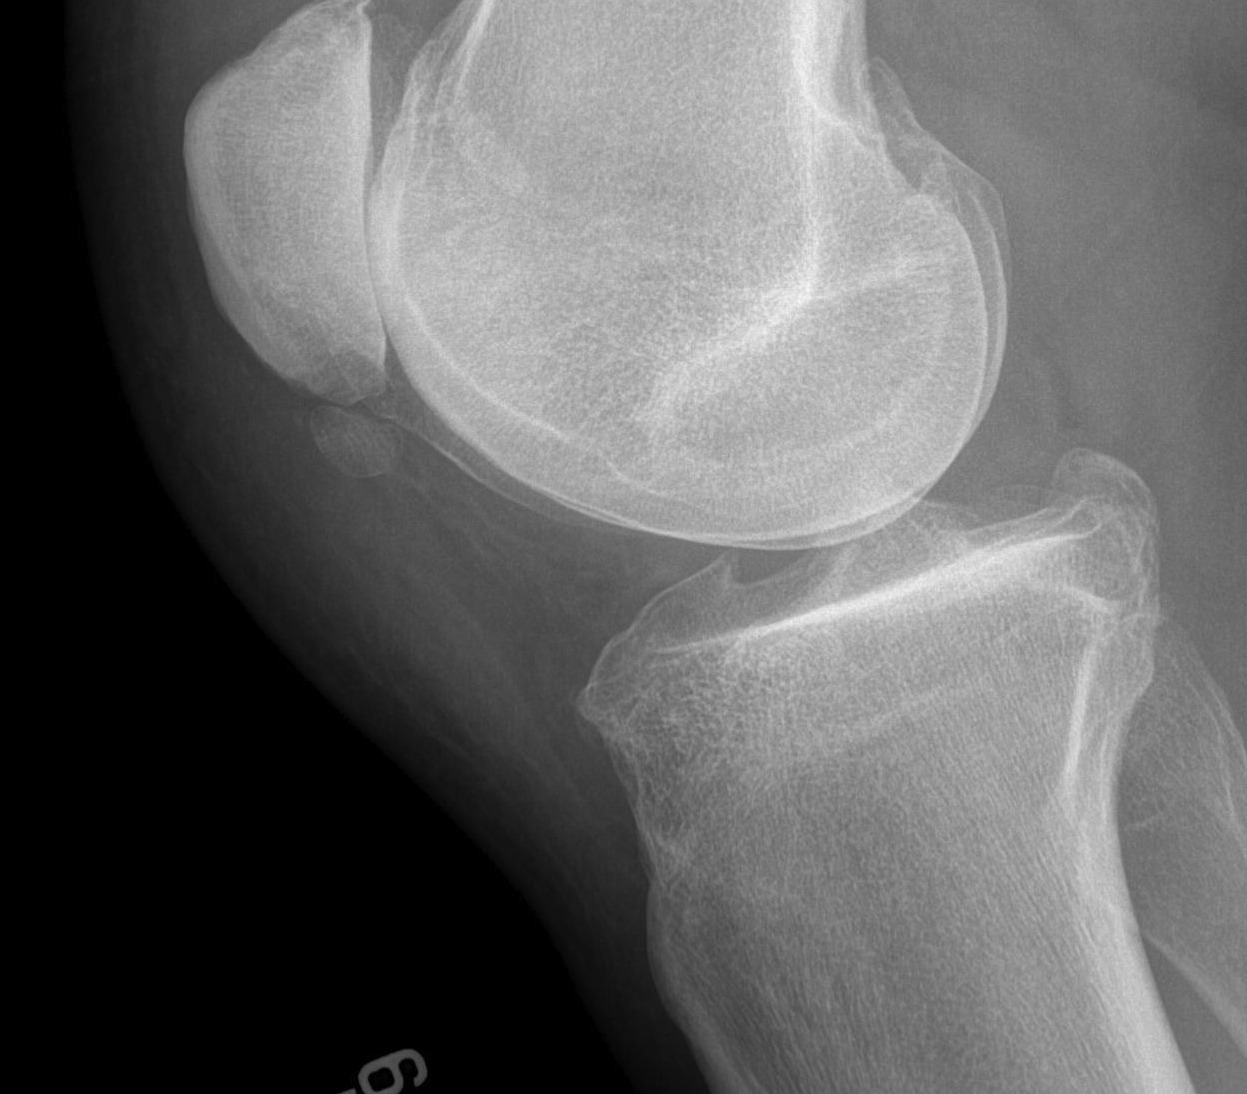

Different Types of Knee Replacement Surgery Meril Life

Different Types of Knee Replacement Surgery Meril Life How Long To Heal Soft Tissue Damage In Knee The first 48 hours after an injury are very important and you can expect the. This is entirely normal and a natural part of your body’s tissue healing process. They may lead to pain, swelling, and restricted mobility. Although study results have been mixed about the effectiveness of this treatment, relief from one or a series of shots may last. How Long To Heal Soft Tissue Damage In Knee.